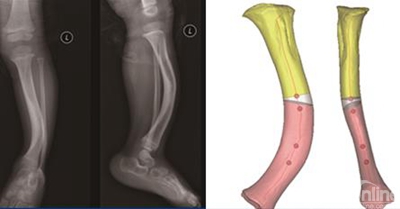

三、个性化导航模板在矫形外科手术的临床应用

我们以下肢骨骼的中心线为标准设计好畸形骨骼的理想力线,通过导航模板的媒介与患者的形态特征及生理功能取得了比较完美的一致性,术后下肢对线得到了明显的改善,并且提高了手术操作的可重复性。根据人体形态学上对称性的原理,通过对四肢力线的测量及镜像理论的应用,基于对骨骼中心线及数学方法的知识,建立了不同部位畸形矫正的个体化导航模板,在临床应用中获得了肯定的效果。

下面选择一例膝关节内翻患者做一介绍。根据镜像原理,建立患侧下肢的镜像模型,通过Three-matic6.1将模型投影到冠状面和矢状面上进行测量。我们选择对胫骨的中心线曲线上曲率最小的一段折线,其两个端点对应点的坐标定义为截骨平面所在的位置。在Three—matic6.1 软件建立健侧胫骨及其镜像模型的中心线,获得胫骨内翻角度(预期截骨角度),可以进行模拟截骨复位,设计个体化矫形方案,生成模板实体指导手术(图16-19)。

附加病例:胫骨畸形儿童一例,利用CT数据获得畸形骨骼的三维模型

基于胫骨中心线呈曲线及曲率的数学概念,选择该中心线上曲率最小的两个点确定截骨平面,再通过反复模拟截骨复位,获得最佳模拟手术的效果,进而建立导航模板。

术中操作,利用克氏针沿导航管道钻出截骨轨道进行截骨、复位、内固定;

术后X影像表现,胫骨轴线得到纠正,形态学上的显畸形得到有效纠正。

研究表明,建立的辅助精确手术的方法能够充分利用骨骼对应力的适应性控制,在矫正骨骼畸形的同时有利于骨的生长与吸收,促进骨骼愈合改建及功能优化重建。对个体化骨骼矫形的术前规划和术后评估具有了极大的启示作用。本文基于畸形骨骼的中心线及其投影,以数字化和量化的数学方法来精确的计算出截骨平面及其角度,保证了实现对畸形骨骼精准矫形的最终目的。